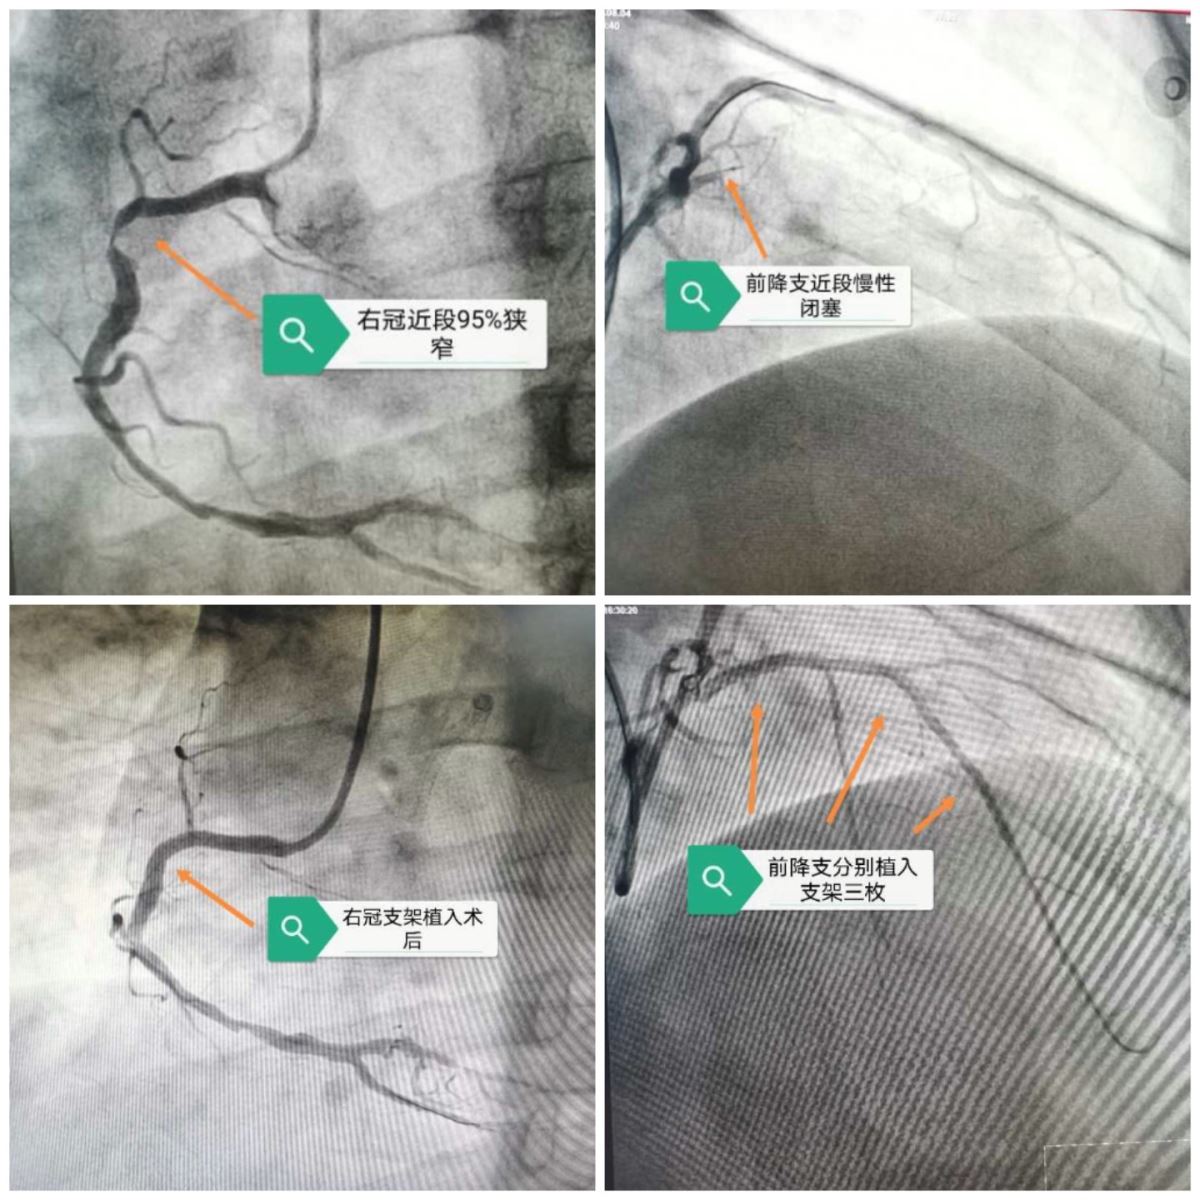

2020年8月3日,患者因反复胸闷痛就诊于我院心内科门诊,行相关检查后,宝云龙主任建议住院进行冠脉造影检查,造影结果显示:前降支近段完全闭塞,回旋支中段70%狭窄,右冠状动脉近段98%狭窄,三支病变!

由于闭塞病变较长,侧支循环差,不能提供较好的寻径依据,只能更多的依靠经验和手感,在适用很多导丝失败后,决定启用头端较硬的进攻导丝,从Fieldet xt逐渐升级到Gaia First,最终升级到Gaia Third,导丝越是坚硬,通过能力越强,但是随之所带来的风险也就越大,一旦不小心穿出冠脉破入心包,患者在台上会危及生命,经过长达3个小时的不懈努力,先后换用6根导丝,终于成功开通闭塞已久的前降支,由于病变较长,闭塞时间较久,累及多个分支血管,开通血管后多处出现夹层,经过后扩、切割、边支保护等多项复杂介入技巧,最终成功植入三枚支架,术后患者状态较好,不适症状消失,心功能得到进一步恢复,患者家属较满意,择期于右冠植入支架一枚。